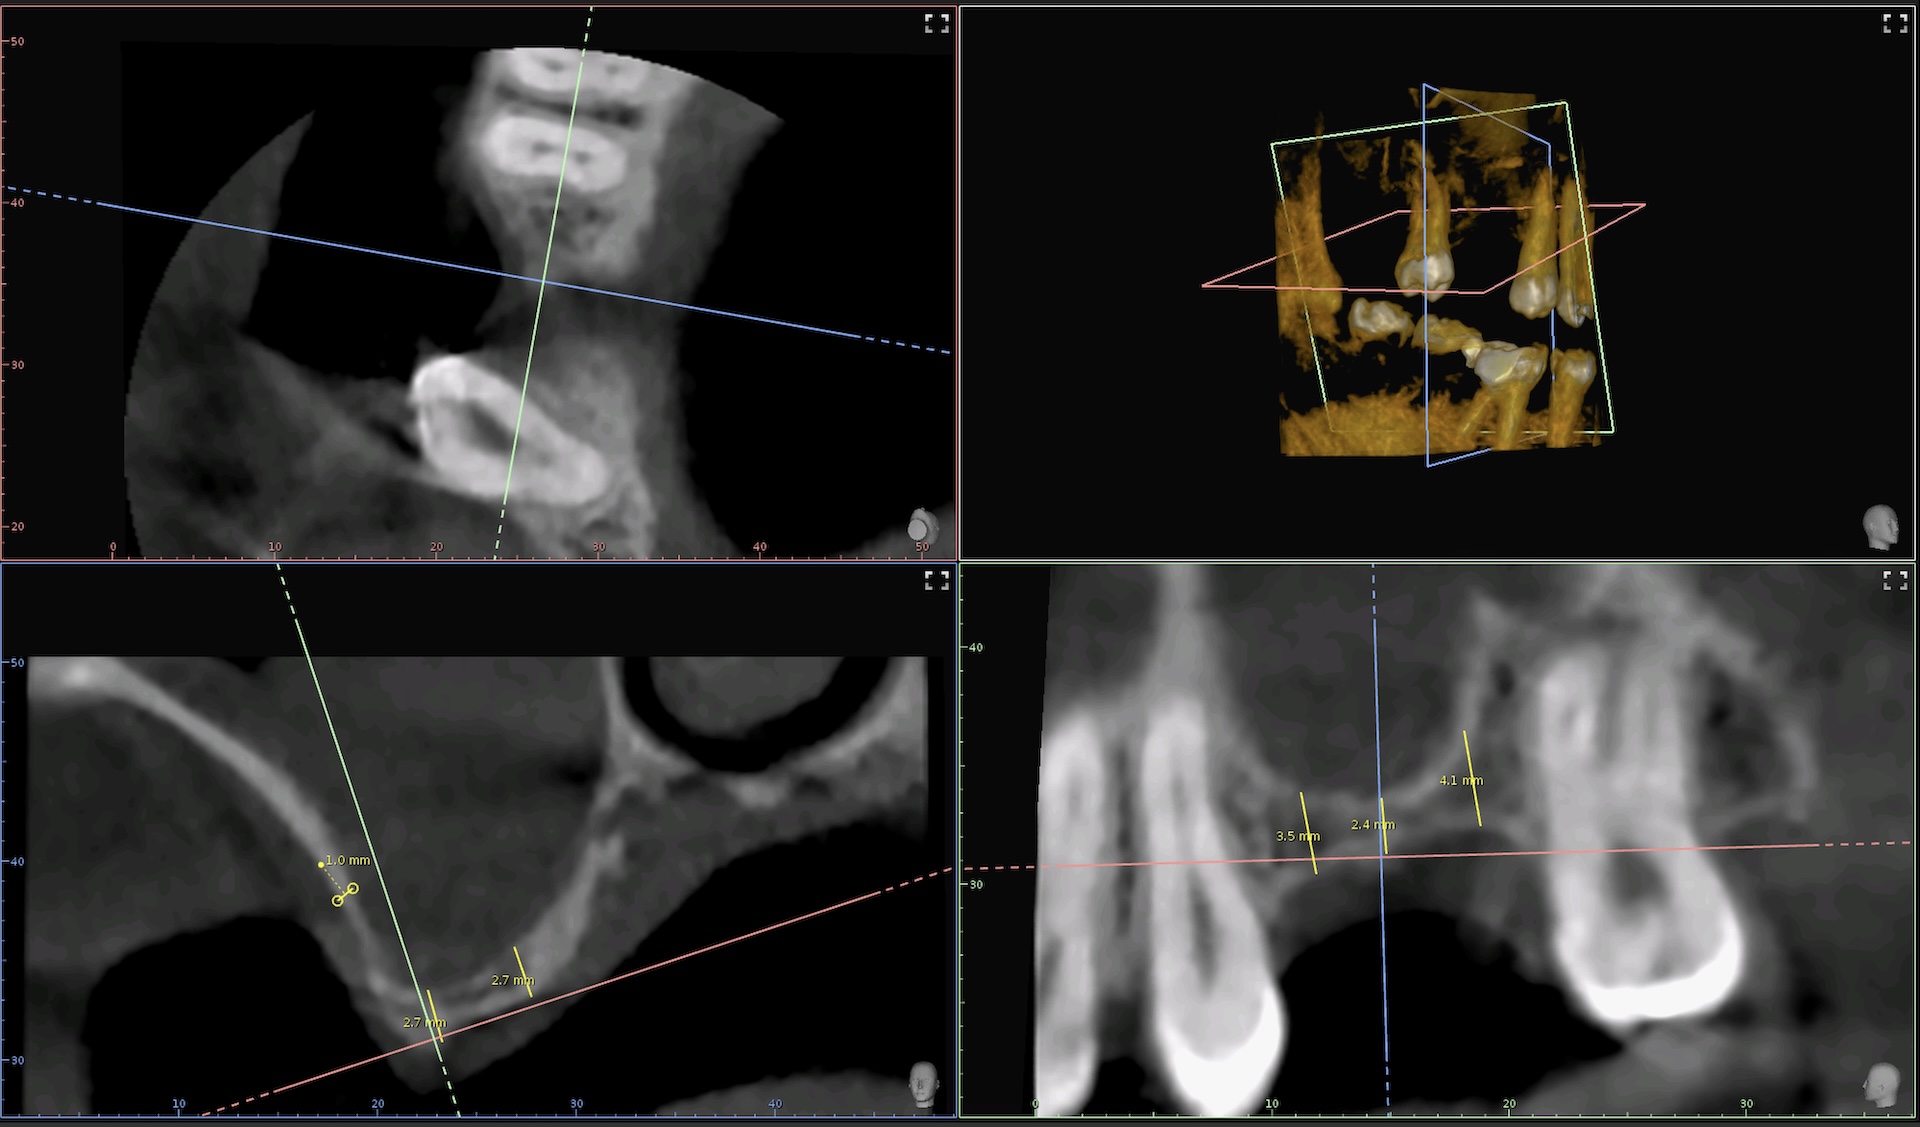

Digitales Röntgen und Volumentomographie

Wir verwenden in unserer Praxis ausschließlich strahlungsarme, digitale Röntgengeräte. Neben einem 3D DVT-Panoramaröntgengerät haben wir in jedem Behandlungszimmer ein eigenes Kleinöntgengerät, mit dem wir alle notwendigen Röntgenaufnahmen zur Diagnose bequem auf dem Behandlungsstuhl durchführen können.

Alle zwei bis drei Jahre sollte eine röntgenologische Kariesfrüherkennungsuntersuchung durchgeführt werden. um Karies auch an versteckten Stellen, zum Beispiel in Zahnzwischenräumen und an unter dem Zahnfleisch liegenden Stellen rechtzeitig erkennen zu können. Durch die 3D Aufnahmetechnik können wir für die Implantologie und für die Endodontologie dreidimensionale Strukturen von Zähnen und Knochen darstellen.

Implantologie

Falls ein Zahn trotz aller Bemühungen nicht erhalten werden kann, bieten sich Implantate als Substanz schon in der Ersatz an. Ein Implantat ist eine künstliche Zahnwurzel, die im Kieferknochen verankert wird. Darauf lässt sich eine Krone befestigen, mit der man wie auf einem natürlichen Zahn kauen kann. Somit kann das Abschleifen von gesunden Zähnen, z. B. für eine Brücke vermieden werden. Durch den Einsatz von dreidimensional Röntgen (DVT) wird eine besonders präzise Implantatsetzung ermöglicht. Man Kann vor der OP den Knochen vermessen und die Lage der Implantate digital planen.